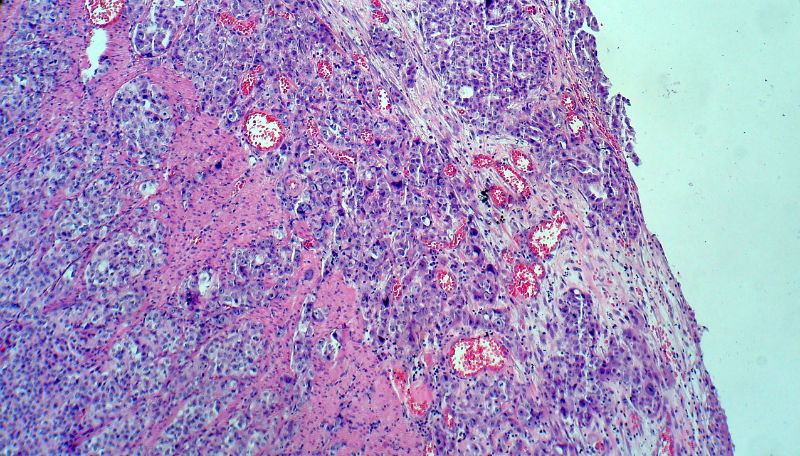

男,82岁,小肠穿孔紧急手术。

大体,小肠一段,长约60厘米,与粘膜面可见三个溃疡型肿物,肠系膜淋巴结肿大。

肿瘤呈巢片状分布,细胞大小相对一致,胞浆丰富,胞核呈细颗粒状,可见小核仁,血管较丰富,考虑神经内分泌肿瘤,加做免疫组化(Ki67、Syn、NSE、CgA、CD56)分级。

腺癌,部分为神经内分泌癌

神经内分泌癌。